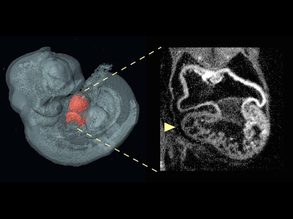

Squeezing the Heart